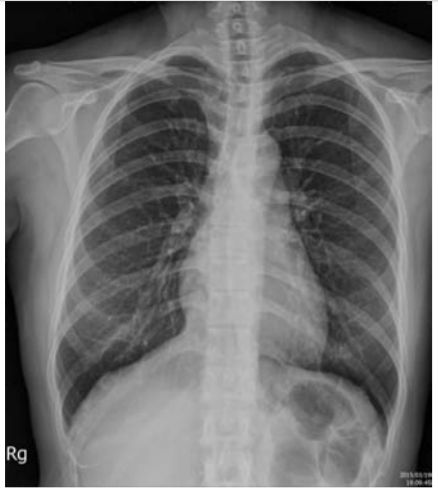

5. 病人男性59歲於午夜24時,突因胸悶並有牙床緊疼,乃直往急診部求診,時病人之T/P/R = 35.1/51/18, BP 137/74 mmHg; 理學檢查,未見任何異常。病史追尋,本病人曾經醫師確定高血壓、高脂血、糖尿病及攝護腺肥大,唯僅只服用Bisoprolol 2.5 mg/day。經緊急檢查:其心電圖及胸部X光顯示如圖:生化檢查: CK,96 U/L;CK-MB,20 U/L;TnI <0.0012 ng/ml;Sugar 252 mg/dL; Na,137 mmol/L; K, 3.7 mmol/L; TG,182 mg/dL and Total cholesterol, 222 mg/dL ; 血液檢查: Hb,13.9 g/dl; Platelet, 203 K/uL; WBC,9.45 K/uL; Cre,1.3 mg/dL 請問本病人最可能的急診診斷是:

(A) Printzmetal's angina (B) Aortic dissection (C) Acute anterior myocardial infarction (D) Hypertension (E) Acute periodontitis disease